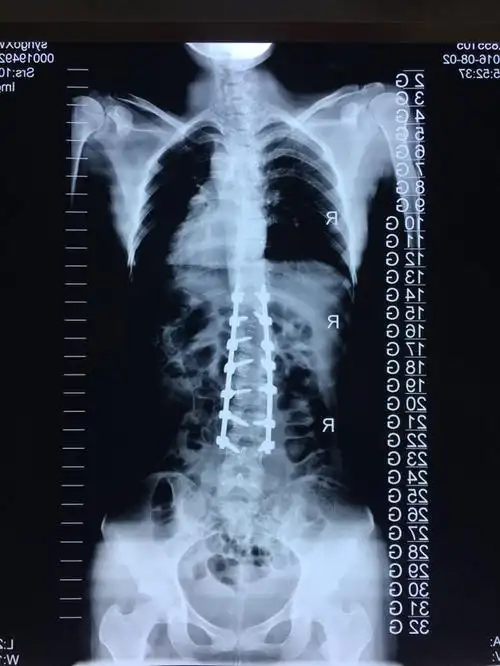

青少年特发性脊柱侧弯之二 - 好大夫在线